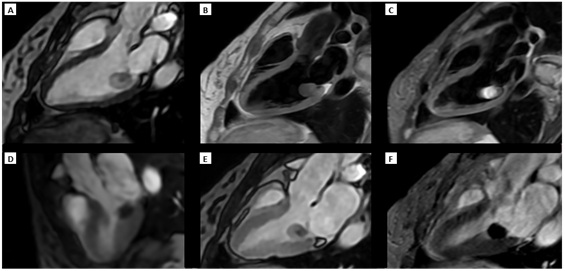

Diagnostic Techniques and Their Most Important Findings: On admission, a transesophageal echocardiogram (TEE) revealed a heterogeneous mass (solid and cystic components), sessile, attached to the ventricular surface of the posterior mitral leaflet, measuring 21.9 x 18.6 mm, with limited mobility, no flow within on color Doppler, and preserved valvular function. The initial presumptive diagnosis was hydatid versus blood cyst (Figure 1).

Figure 1. TEE findings: A) Mid-esophageal at 0°, four-chambers view and B) Transgastric at 0°, short axis view at mitral valve level: sessile mass with mixed content attached to the ventricular surface of the posterior leaflet of the mitral valve, with no color Doppler flow within.